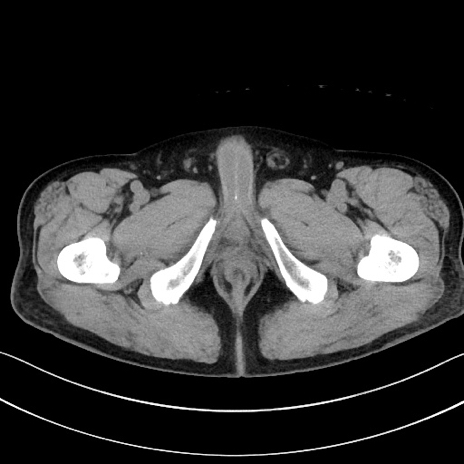

症例15(横断像)

【症例】70歳代男性

【主訴】腹痛

【現病歴】今朝から腹痛あり。全体的に痛い。特に左上の方。排ガスが今日はない。冷や汗が出る。

【既往歴】直腸癌術後

【身体所見】左側腹部〜上腹部に圧痛あり。腹膜刺激症状明らかなではない。軽度反跳痛。左下腹部に術後瘢痕あり。

【データ】WBC 7700、CRP 0.02